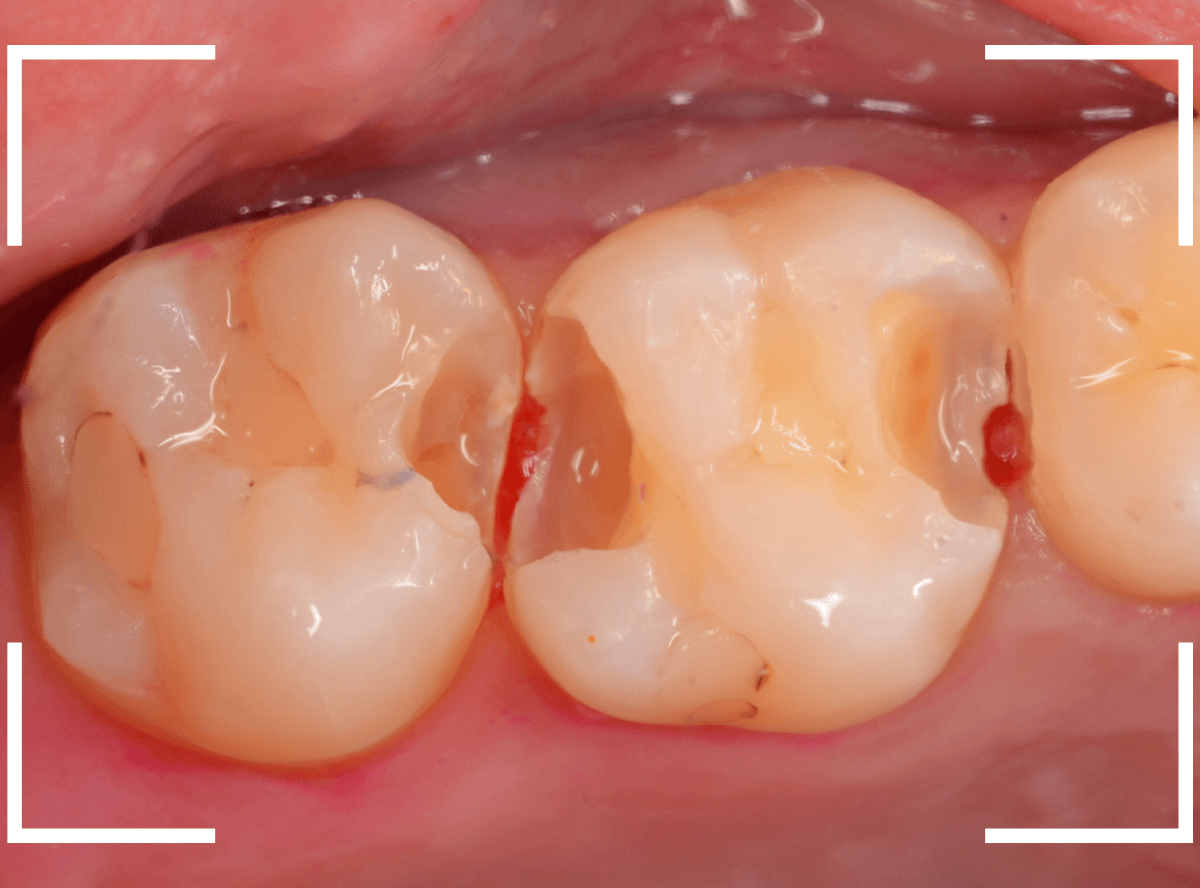

Case.23 歯のすきまから両側が大きな虫歯

「下の奥歯が痛む」という訴えで来院された患者さんのケースです。

目視でも、手前の奥歯がかけていて、中で虫歯が広がってるであろうことは予想できます。

ピンセットで歯を叩いてみても、手前の奥歯が痛むようです。

レントゲン写真で確認します。

状況から、まず手前の奥歯から治療となりました。

麻酔をして、手前の奥歯のレジンを慎重に外します。

前に虫歯の治療をした時点で、神経スレスレの状態でしたので、削りすぎないように慎重にレジンを外さなければいけません。

レジンを外して、う蝕検知液で確認します。

レジンの中で虫歯が進行していたのがわかります。

慎重に全ての虫歯を除去しました。

何とか、神経が露出せずに済んでいます。

お薬をつめて、セメントで蓋をして経過観察します。

後日、状況を確認したところ、虫歯処置した後も、手前の奥歯が痛むとの事でした。

「我慢できないほどでもない」との事でしたので、引き続き経過観察しつつ、奥歯の治療を治療する事になりました。

奥歯は、レントゲンで見た通り、少し歯を削るとすぐに虫歯の穴が出てきました。

こちらは、ある程度虫歯を取ったところで染め出してみると真っ赤です。

ですが、何とか神経に達する前に、全ての虫歯を除去できました。

神経の治療が必要かと思っていたので、その点は幸運でした。

奥歯もお薬をつめて、セメントで蓋をして経過観察です。

何とか神経を取らずに済ませたいですが、どうなる事か・・・。